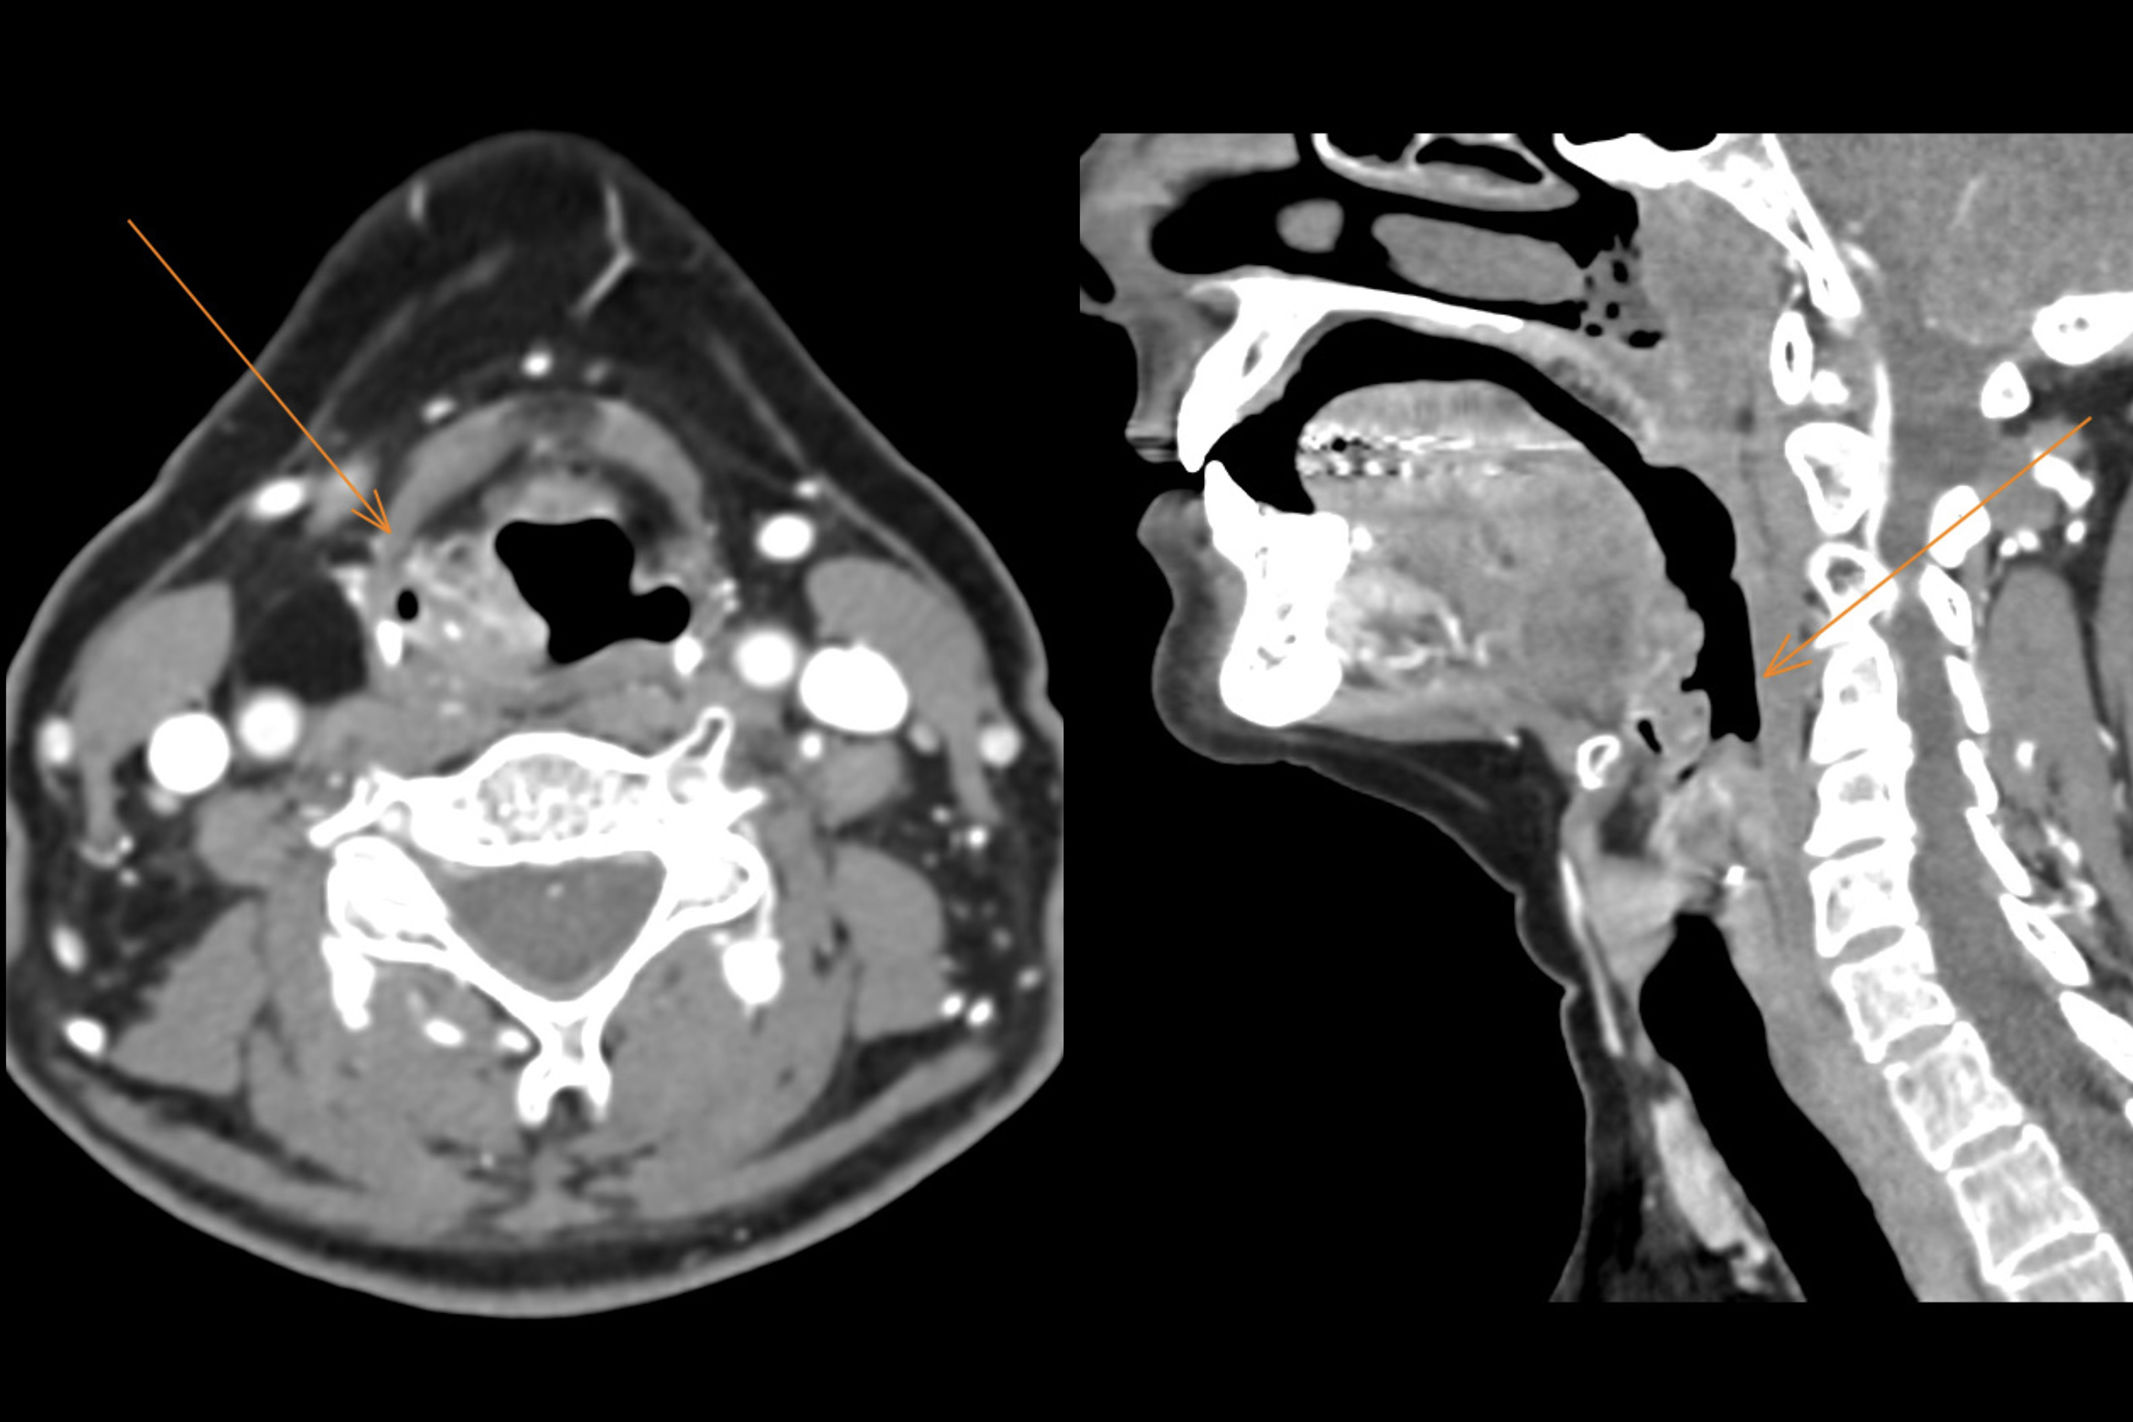

Figures (1)